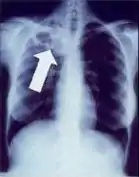

Chest X-ray and CT

In active pulmonary TB, infiltrates or consolidations and/or cavities are often seen in the upper lungs with or without mediastinal or hilar lymphadenopathy or pleural effusions ( tuberculous pleurisy). However, lesions may appear anywhere in the lungs. In disseminated TB a pattern of many tiny nodules throughout the lung fields is common - the so-called miliary TB. In HIV and other immunosuppressed persons, any abnormality may indicate TB or the chest X-ray may even appear entirely normal.

Abnormalities on chest radiographs may be suggestive of, but are not necessarily diagnostic of, TB. However, chest radiographs may be used to rule out the possibility of pulmonary TB in a person who has a positive reaction to the tuberculin skin test and no symptoms of the disease.

Cavitation or consolidation of the apexes of the upper lobes of the lung or the tree-in-bud sign[8] may be visible on an affected patient's chest X-ray.[1] The tree-in-bud sign may appear on the chest CTs of some patients affected by tuberculosis, but it is not specific to tuberculosis.[8]